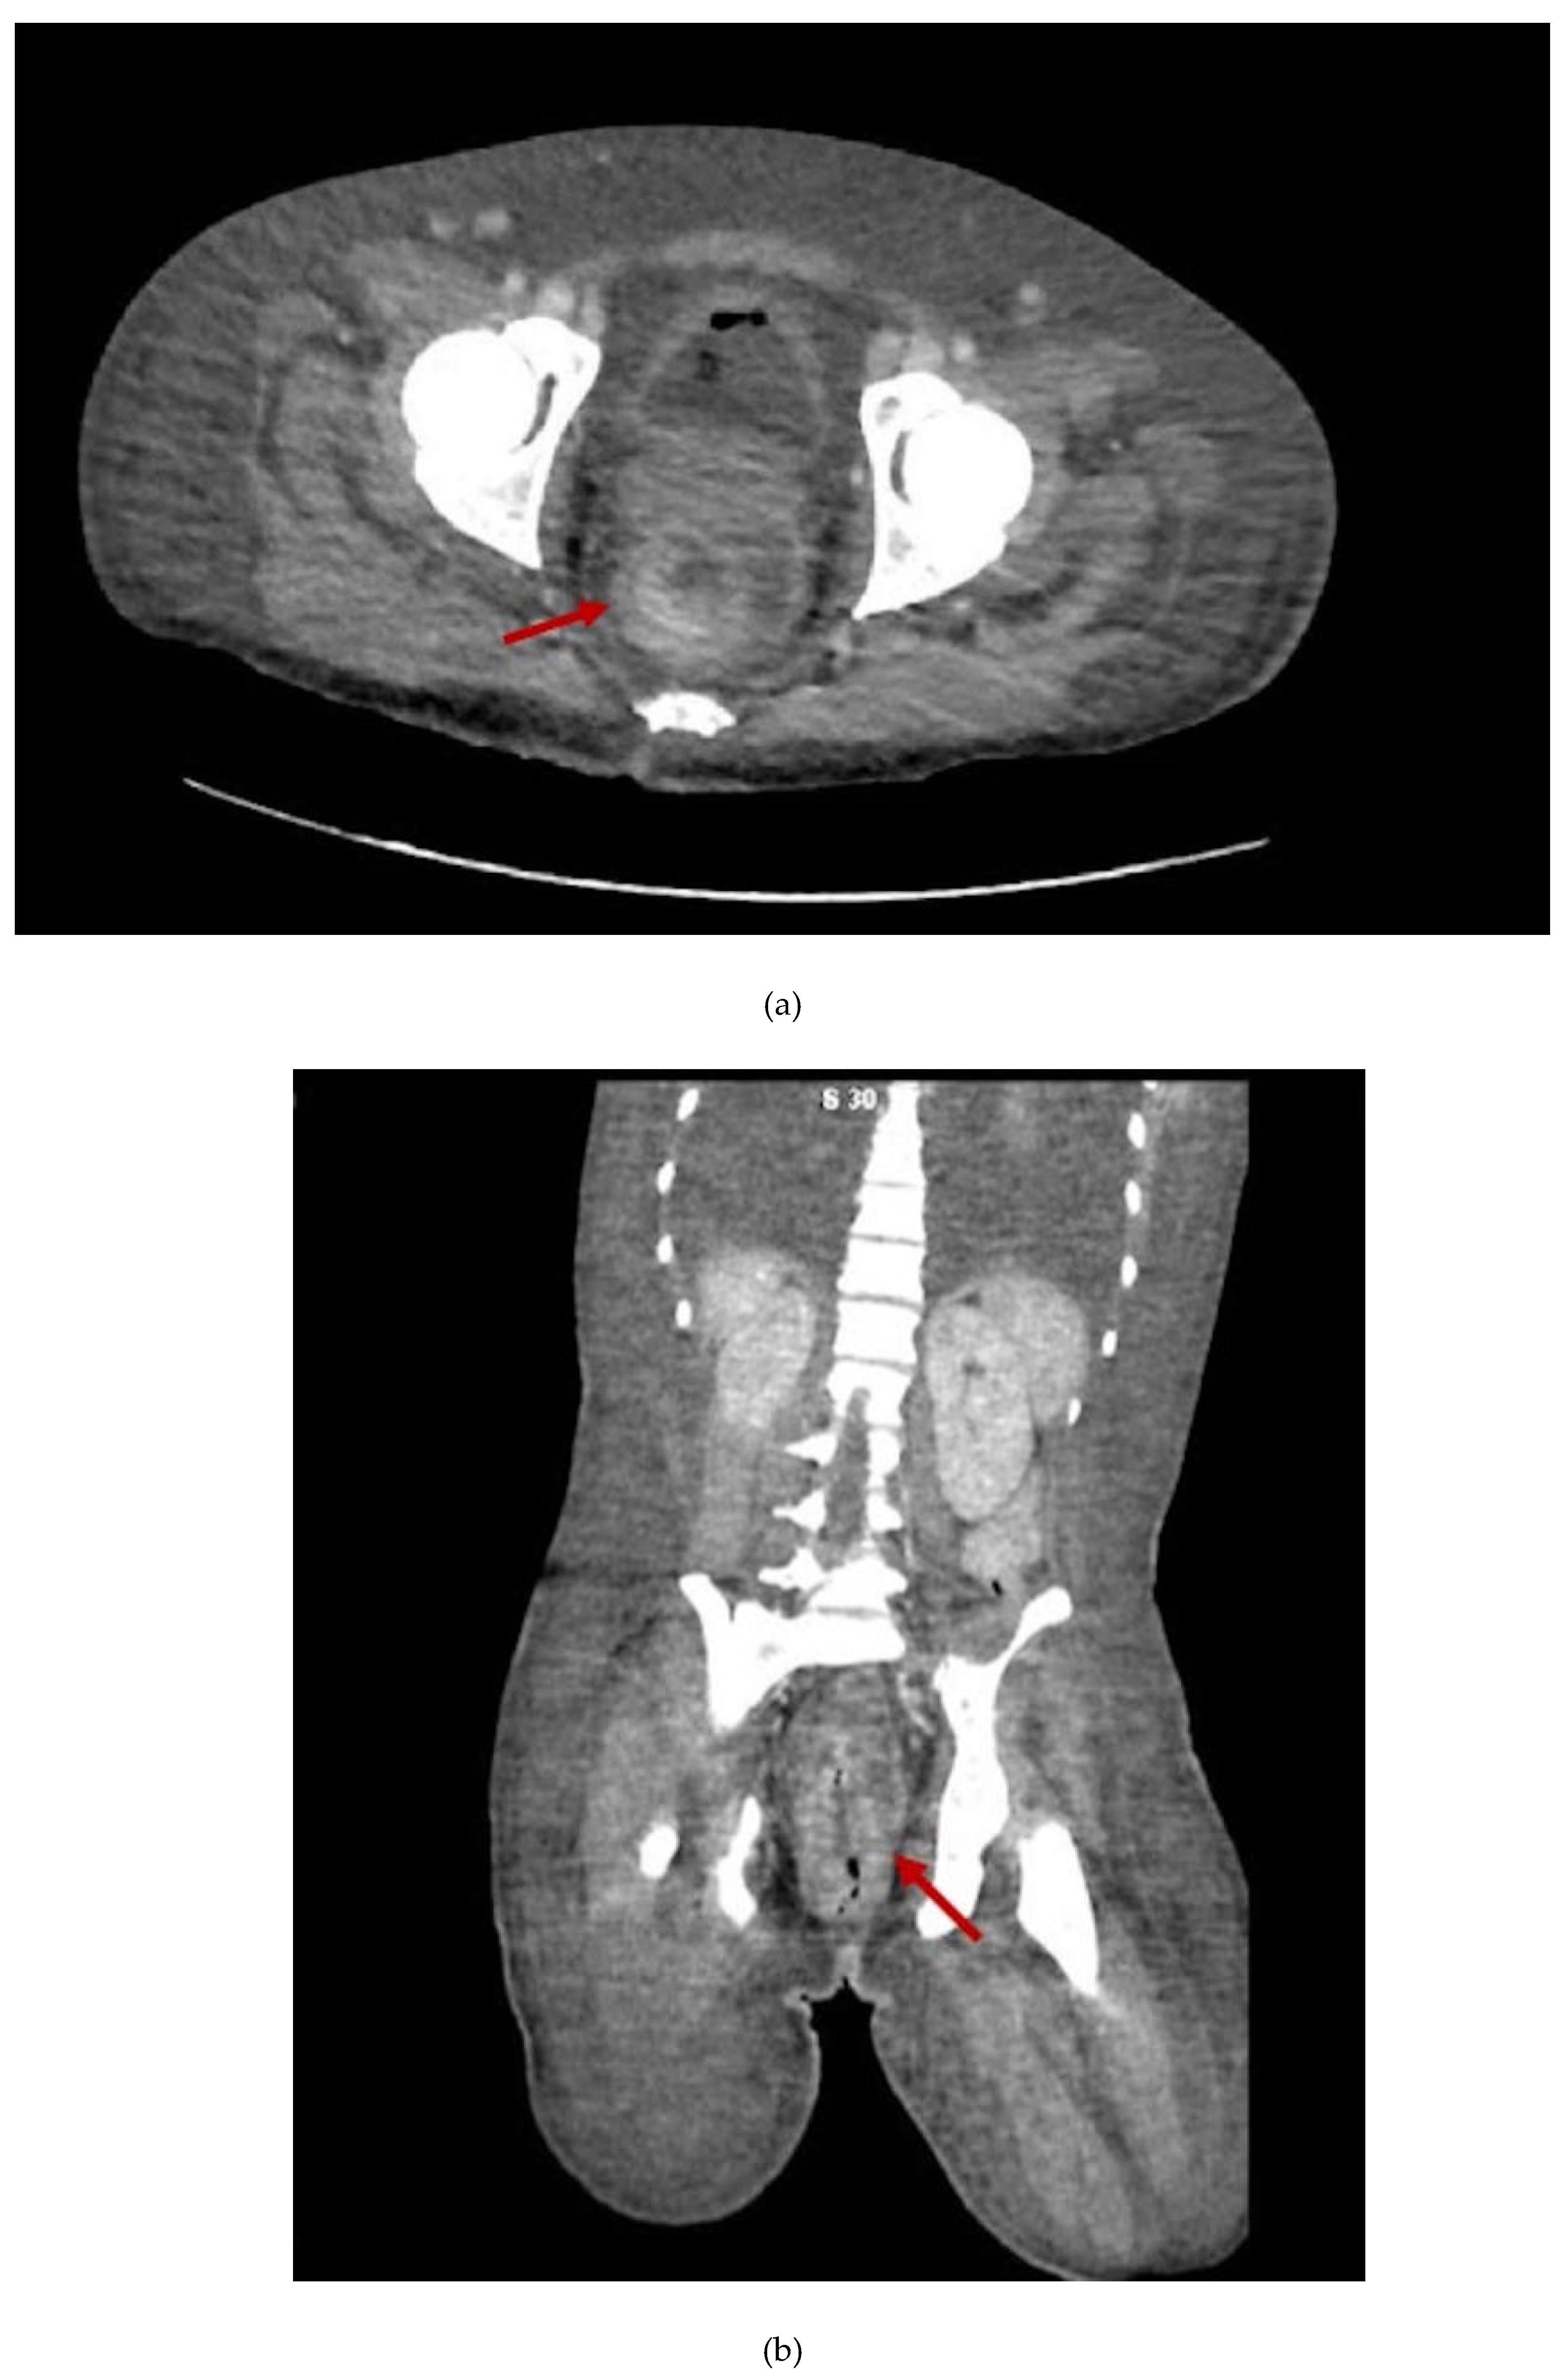

2. Case Presentation Section